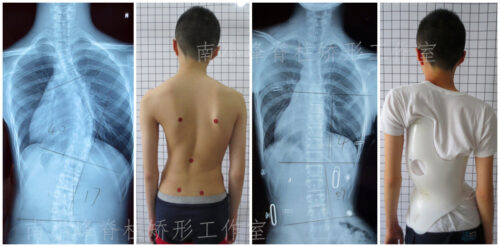

ما هو العمر الأكثر خطورة للإصابة باعوجاج العمود الفقري؟ سؤال يشغل بال الكثير من الأهل، خاصة عندما يلاحظون تغيرًا في شكل ظهر أو كتف طفلهم. اعوجاج العمود الفقري أو الجنف هو حالة طبية تتميز بانحناء غير طبيعي للعمود الفقري، وقد تظهر في أي عمر، لكن هناك مراحل عمرية يُعتبر ظهور المرض فيها أكثر خطورة من غيرها. في هذا المقال، سنوضح بشكل مبسط متى يظهر الجنف عادةً، ومن هم الأكثر عرضة، ولماذا تختلف خطورته بين الأطفال والبالغين.

تشخيص الجنف في مراحله المبكرة ليس أمرًا سهلاً. في البداية، قد لا يظهر الانحناء بوضوح، خاصة إذا كان بسيطًا. غالبًا يتم اكتشاف الحالة عندما يزداد الانحناء ليؤثر على شكل الجسم أو وضعية الأكتاف والحوض. ولهذا السبب قد تمر سنوات قبل أن يعرف الأهل أن طفلهم مصاب بالجنف.

تشير الدراسات الطبية إلى أن الأطفال في سن 11 إلى 15 عامًا هم الأكثر عرضة لخطورة تطور الانحناء. والسبب هو أن هذه المرحلة تمثل فترة البلوغ والنمو السريع، حيث يزداد طول الطفل بشكل ملحوظ خلال وقت قصير.

عند الأطفال والمراهقين: الخطر الأكبر هو سرعة تطور الانحناء مع النمو. فمثلاً، إذا تجاوز الانحناء 30 درجة قبل سن 10 سنوات، فإن احتمالية التفاقم تصل إلى 100% إذا لم يتم التدخل. هذا قد يؤدي في النهاية إلى الحاجة لجراحة أو ظهور تشوهات واضحة.

في حال ملاحظة أي من هذه العلامات، يجب استشارة الطبيب على الفور لعمل فحص سريري وتصوير بالأشعة إذا لزم الأمر.

متى يحتاج الطفل المصاب باعوجاج العمود الفقري إلى علاج؟

إذا كان الانحناء بسيطًا، قد يكتفي الطبيب بالمتابعة الدورية.

إذا كان الانحناء متوسطًا، قد يوصى باستخدام الحزام الطبي PioBrace الذي يساعد في تصحيح الانحناء ومنع تطوره.

في الحالات الشديدة التي لا تستجيب للعلاج غير الجراحي، قد يتم اللجوء إلى الجراحة.